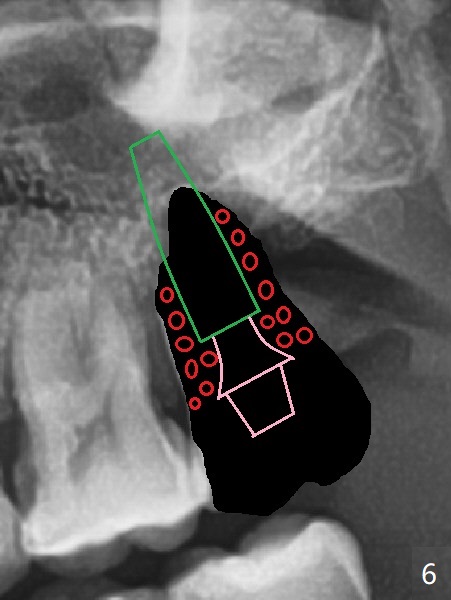

步骤三:植骨(图六:红色)。